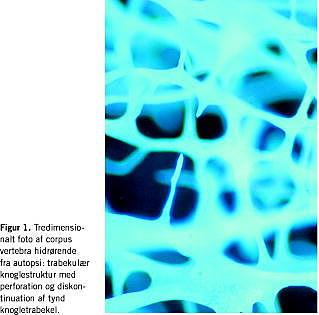

Forskning har vist, at osteoporotisk fraktur er et resultat af nedsatte biomekaniske egenskaber i knoglevævet og især i det trabekulære knoglevæv. Det har længe været kendt, at en af årsagerne til den nedsatte styrke var reduktion i knoglemassen. Dette er imidlertid ikke den eneste patofysiologiske baggrund. Gennem strukturelle stereologiske analyser af store knoglematerialer har det været muligt at belyse knogleomsætning, knoglemasse og især den altafgørende struktur hos hhv. »normale« og osteoporotiske individer og derigennem få indsigt i ikke blot osteoporosens patologi, men også dens patofysiologi. Disse undersøgelser [9] har således vist meget nær relation imellem knoglestyrke og knoglestruktur, sidstnævnte estimeret som orientering og konnektivitet af bjælkerne i det trabekulære knoglevæv (Figur 1 ). Endvidere har undersøgelser af store materialer givet mulighed for klassifikation af primær og sekundær osteoporose, som såvel patofysiologisk som behandlingsmæssigt er ganske forskellige.